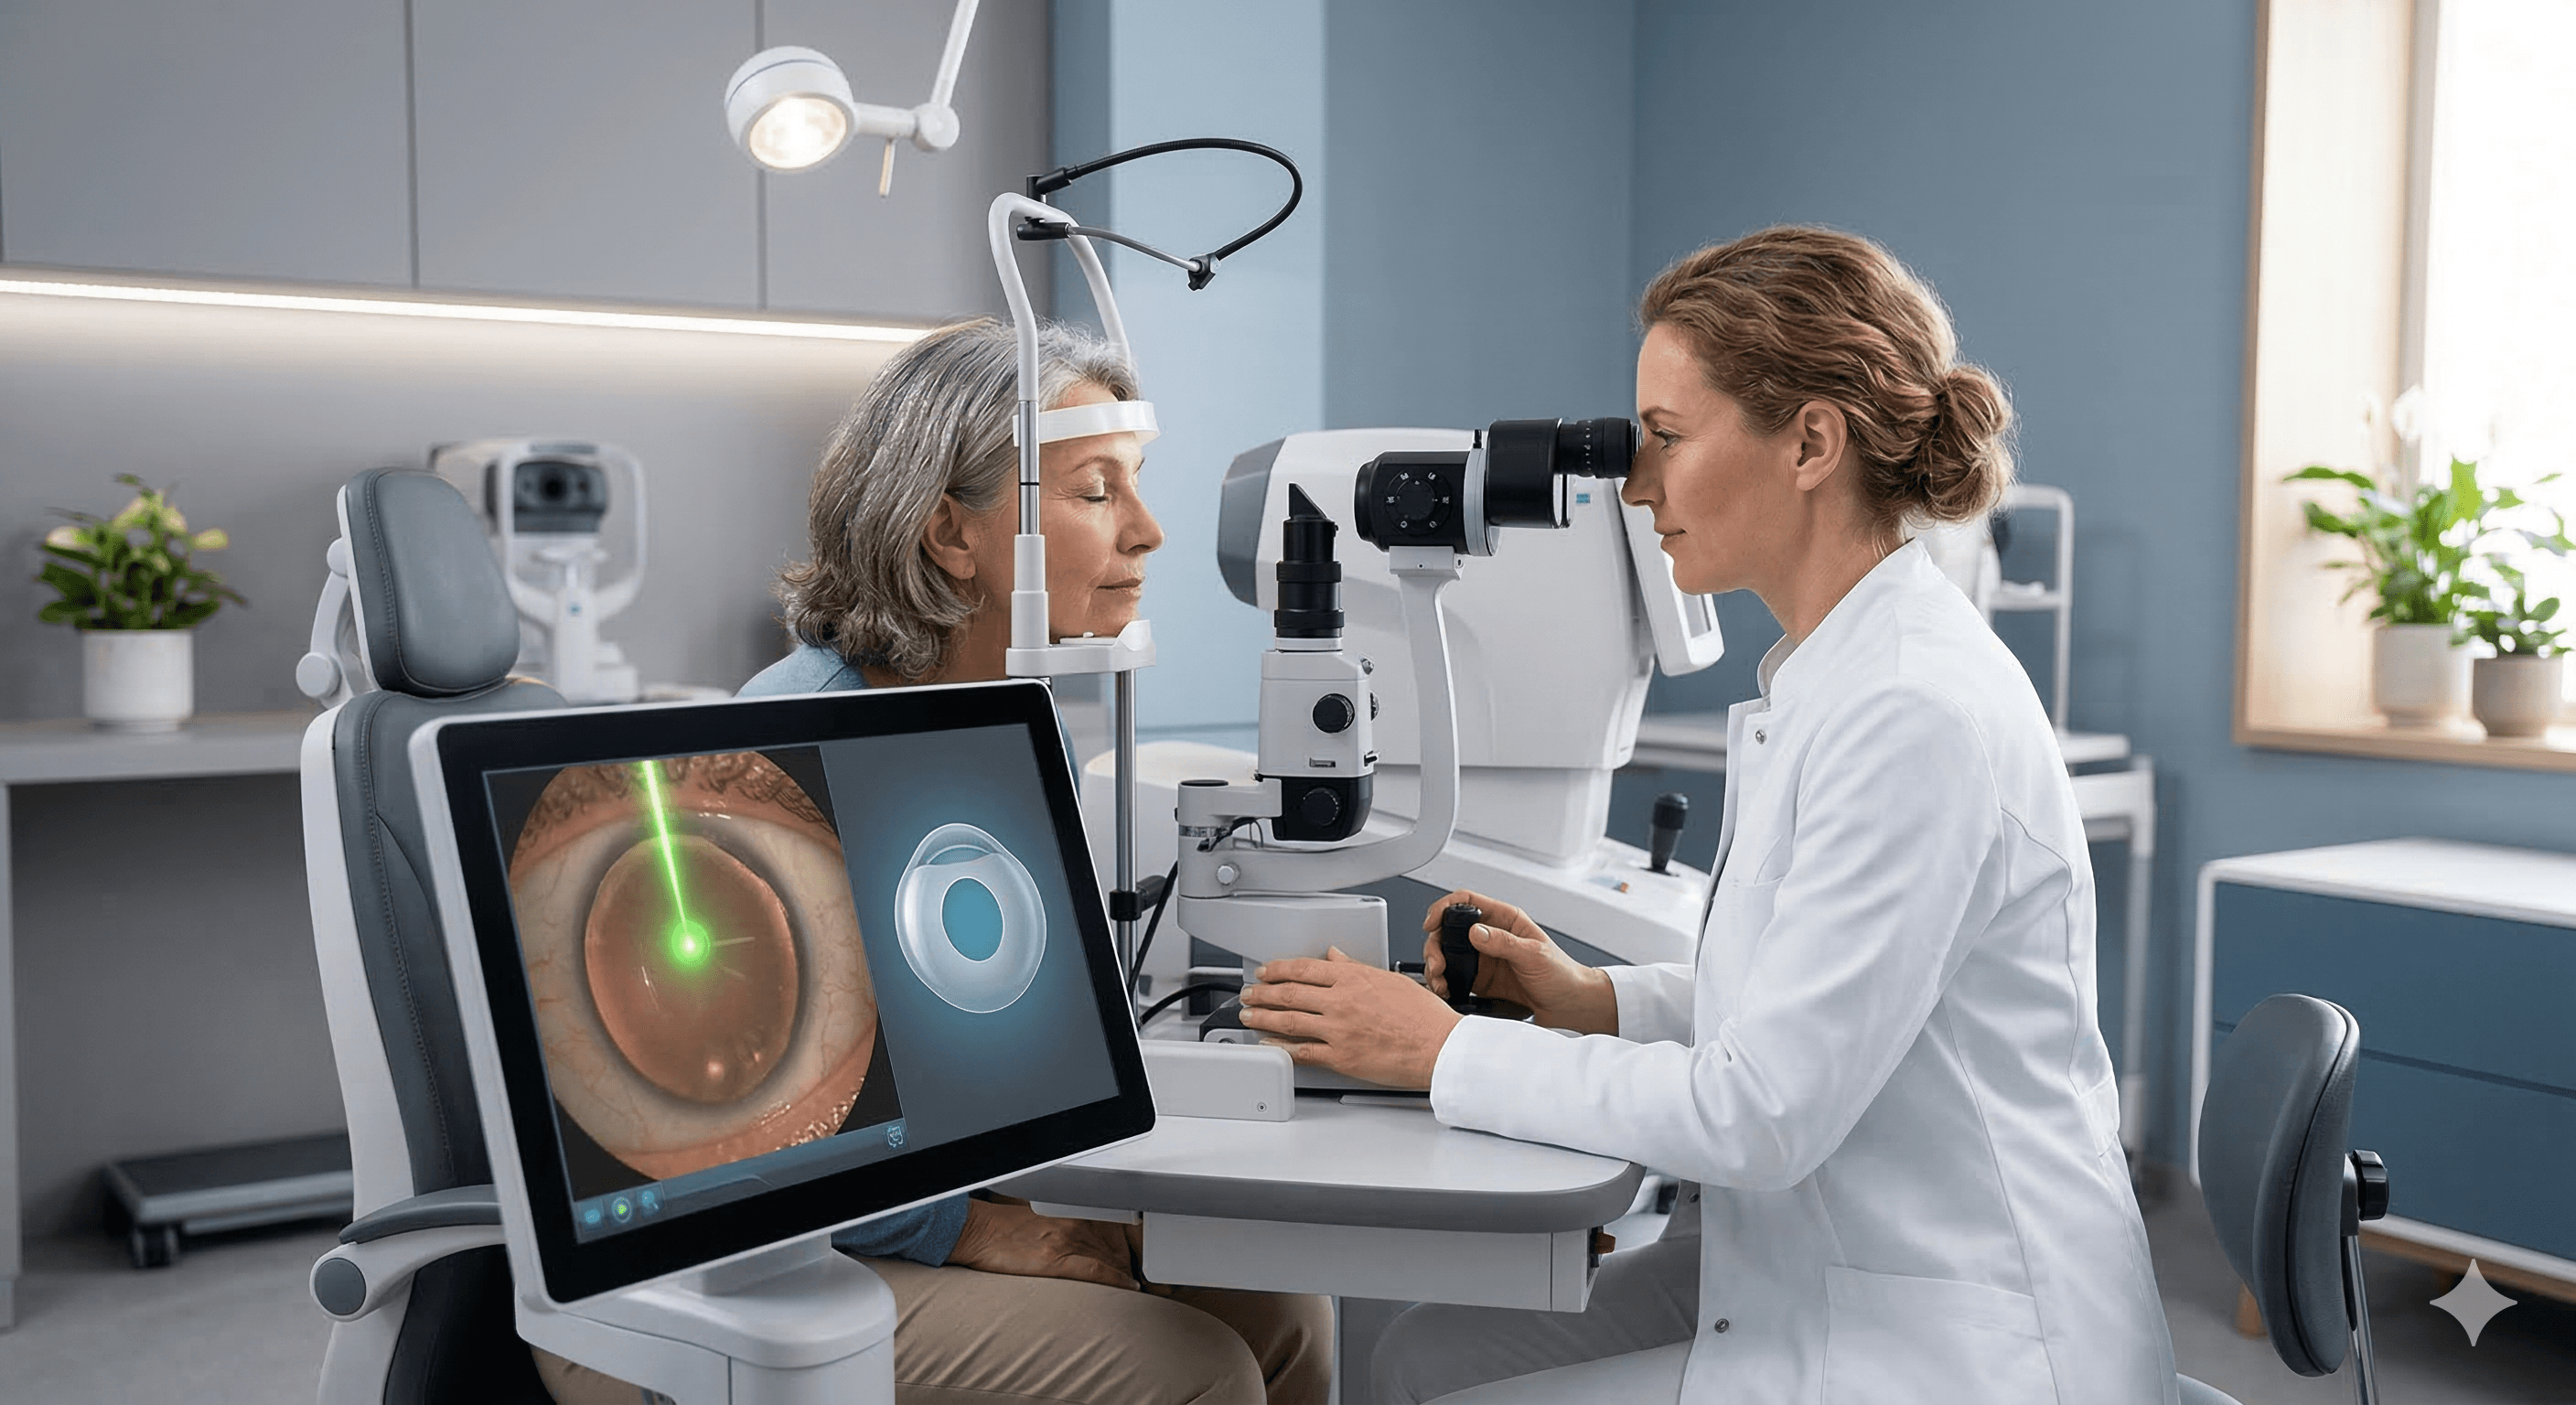

Cirugía de Catarata

LASIK y Cirugía Refractiva

Inversión en tu salud visual

Obtén un diagnóstico preciso y un tratamiento personalizado con tecnología de vanguardia para el cuidado de tus ojos.